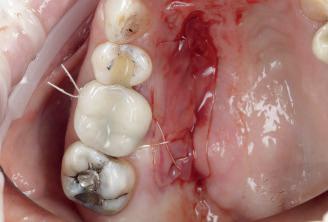

Case 1: Anterior tooth restoration with composite

Case 2: Posterior tooth restoration with composite

Restorations with Beautifil II LS, Beautifil Flow Plus X and OneGloss by Erik-Jan Muts, M.Sc., Netherlands